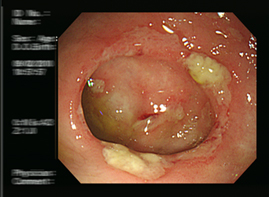

대장내시경은 대장암을 90% 이상 선별하는 방법으로 알려져 있어요. 대장 내시경 검사 시 실제로 암이 발견되면 정밀 검사를 받아야 해요. 먼저 정확한 진단을 받기 위하는 것은 대장내시경 전 식품 유의사항을 정확히 지키는게 중요해요. 식품 유의사항을 잘 지켰다면 병원을 방문하여 검사를 받게 되는데, 검사 시 편한 옷을 갈아입고, 왼쪽 방향으로 옆으로 누운 다음 무릎을 구부린 자세를 취해요. 그다음은 수면 내시경으로 진행한다면 진정제를 투입하면 잠이 들면 항문을 통해 의료 내시경을 삽입하여 검사를 하게 되어요. 비수면의 경우 내시경 삽입 시 강력한 힘이나 말을 하게 되면 삽입이 어려울 수 있기 때문에 긴장을 가능한 한 풀고 진행하게 되어요. 검사 시간은 환자에 따라 조금씩 다르지만 20-30분 정도 소요된다고 해요.